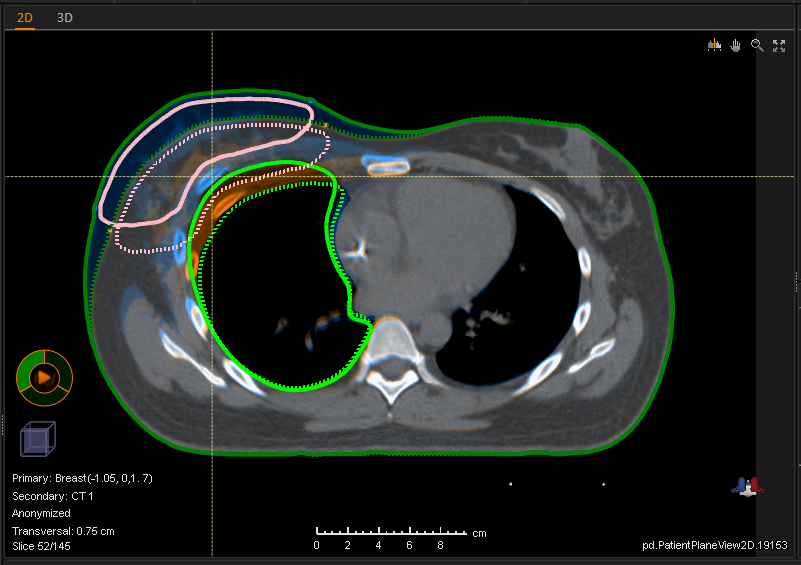

Many particle centers worldwide are using RayStation for their proton planning. Probably because RaySearch has been, and continues to be pioneers in cutting edge proton planning techniques. Highlights in RayStation®* 11B include:

RayStation provides leading tools for designing and optimizing actively scanned pencil beams. Optimization strategies include our pioneering scenario based robust optimization, robust Multi Criteria Optimization, and robust 4D optimization. Accurate dose computation in optimization and final dose is achieved using our lightning fast GPU based Monte Carlo dose engine. RayStation also support PBS planning using patient specific apertures or MLC collimation. The robustness of the optimized plans can be assessed using the dedicated Plan Robustness Evaluation module.

• Spot visualization with beam’s-eye-view and patient 2D/3D views

• Line segment filtering in optimization with beam’s-eye-view and patient 2D/3D views